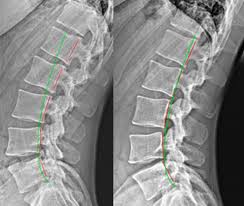

Digital X-Rays for Chiropractic Care are advanced imaging tools that use electronic sensors instead of traditional photographic film to capture detailed images of the spine, joints, and surrounding structures. These high-resolution images are instantly available on a computer, allowing chiropractors to analyze them in real time.

Unlike conventional X-rays, digital imaging eliminates the need for chemical film processing and significantly reduces radiation exposure. Chiropractors can adjust image brightness, contrast, and magnification to get a clearer and more accurate view of a patient’s spinal alignment and joint health.

Digital X-Rays for Chiropractic Care help practitioners identify these issues with greater accuracy. The detailed images allow chiropractors to see how each vertebra is positioned, evaluate disc spacing, and detect potential sources of nerve interference. This deeper understanding ensures that every adjustment and treatment plan is tailored to the patient’s unique spinal structure.

When patients can see what’s happening inside their body, it transforms the way they understand their condition. Digital X-Rays for Chiropractic Care allow chiropractors to show patients detailed images of their spine, point out misalignments, and explain how these issues affect overall function.

Chiropractic care often involves ongoing adjustments and postural corrections. With Digital X-Rays for Chiropractic Care, chiropractors can take follow-up images to track spinal changes and measure improvement.

Seeing these visual results can be very motivating for patients. It confirms that the treatment plan is working and encourages continued care to maintain proper alignment and prevent future problems.

For example, if the images reveal a significant curvature or misalignment in the lumbar spine, the chiropractor can design a targeted plan to correct that specific issue. In other cases, digital imaging might uncover early signs of arthritis or disc degeneration—allowing the chiropractor to recommend gentle adjustments and supportive therapies to protect joint health.